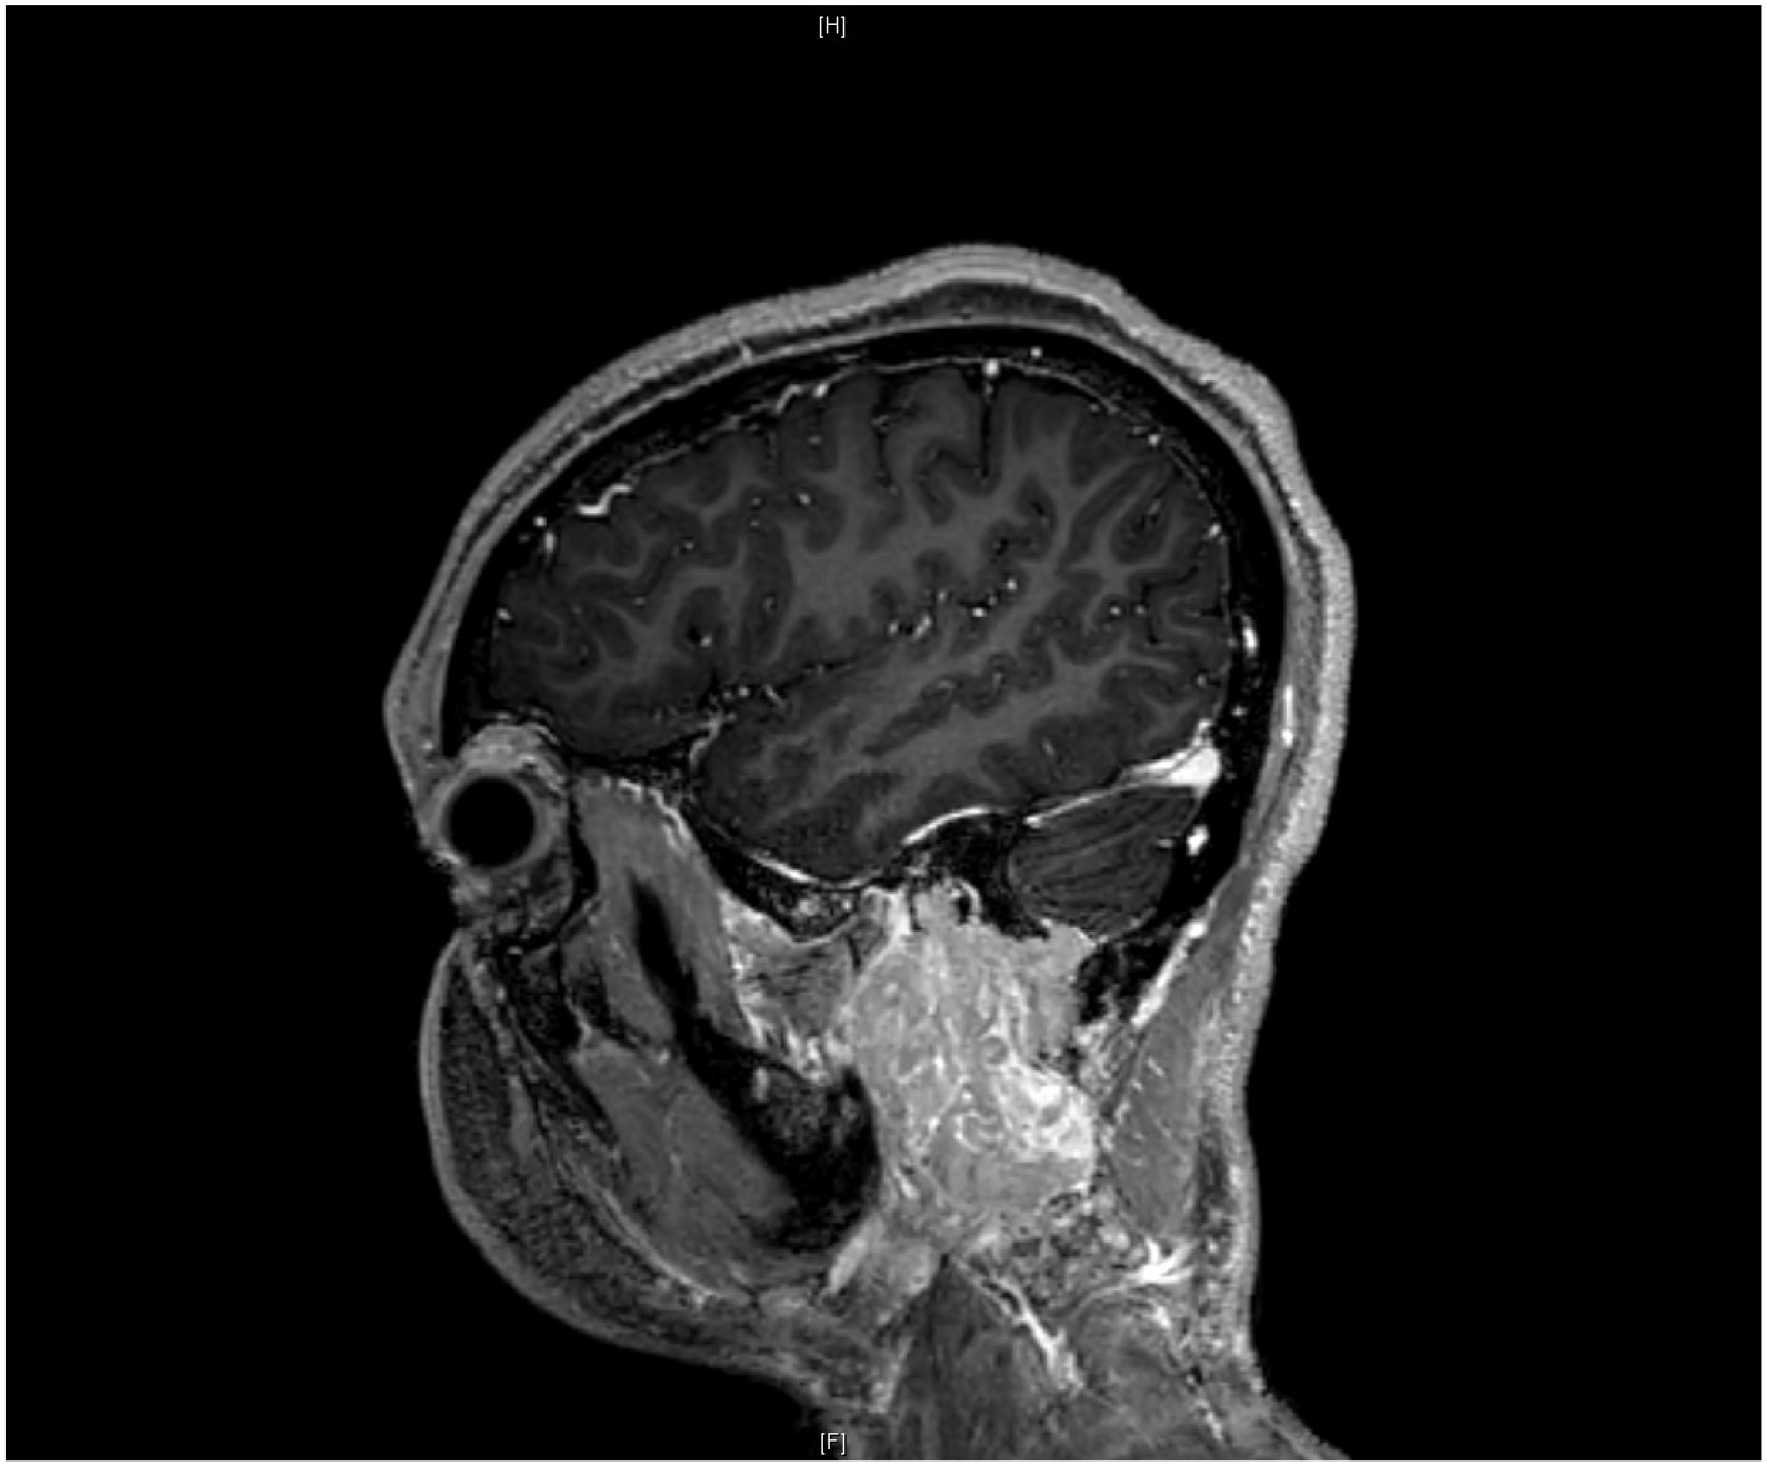

Molecular and Genomic Profiling of Head and Neck Tumors

- PI: Richard V. Smith, MD

- Sponsor: Montefiore Einstein